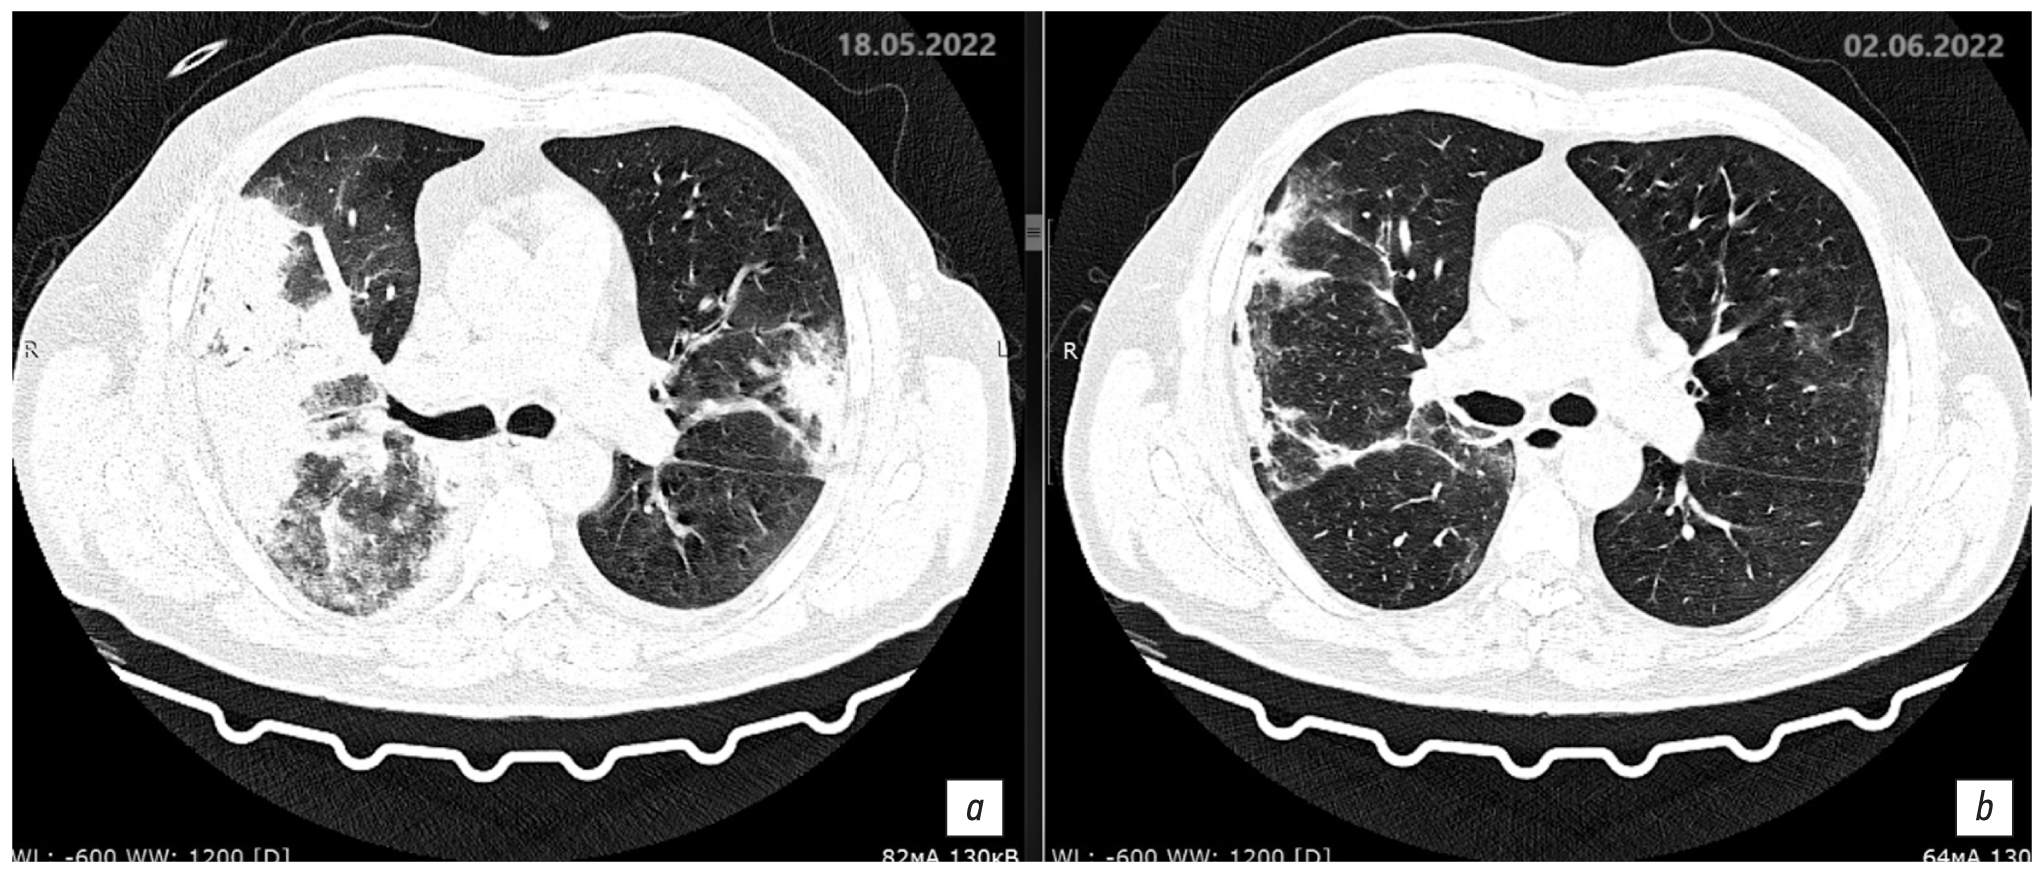

Description of the chest CT scan dated May 18, 2022, day 8 of the disease, day 3 of hospitalization (Fig. 7a, 8a). The lungs display negative infiltrative changes, with increasing extent and size, and new infiltration areas occurred in the lower lobe of the right lung. The lungs are fully expanded. Multiple segments of the lungs exhibit extensive confluent areas of heterogeneous infiltration of the consolidation type with a peripheral rim of ground glass are observed, with visible bronchial lumen. Focal masses with somewhat radial contours, measuring up to 3.8 × 5.1 mm and 7.9 × 6.2 mm, are observed in the upper S2 segment on the right side. The bronchial lumen is patent, and the intrathoracic or axillary lymph nodes are not enlarged. Free fluid in the pleural cavities is observed on both sides. On the right side, the fluid extends up to 7–8 mm (previously 5–6 mm), whereas on the left side, the fluid reaches up to 6 mm (previously 2–4 mm). The heart is unremarkable. Results: CT pattern of negative changes in bilateral multifocal pneumonia and bacterial disease (legionellosis?). Focal lesions in the right lung without changes and minor bilateral hydrothorax with slightly negative changes.

Fig. 7. Axial sections showing changes at the level of the upper parts of the lungs over time, pulmonary window: a: chest CT scan dated May 18, 2022, day 8 of the disease, day 3 of hospitalization; b: chest CT scan dated June 2, 2022, day 23 of the disease, day 17 of hospitalization.

Fig. 8. Axial sections showing changes at the level of the lower parts of the lungs over time, pulmonary window: a: chest CT scan dated May 18, 2022, day 8 of the disease, day 3 of hospitalization; b: chest CT scan dated June 2, 2022, day 23 of the disease, day 17 of hospitalization.

The therapy was adjusted to add intravenous azithromycin 500 mg daily. Levofloxacin and azithromycin were continued for a period of 14 days. Gradual improvement was observed. On day 17 of the disease, May 28, 2022, the patient’s condition was of moderate severity, the improvement was due to decreased respiratory failure symptoms. Blood chemistry results improved: CRP 6.0 mg/L, urea 4.7 mmol/L creatinine 89 μmol/L, WBC 6.5 × 109/L, and lymphocytes 3.8 × 109/L.

Description of the chest CT scan dated June 2, 2022, day 23 of the disease, day 17 of hospitalization (Fig. 7b, 8b). Compared to the previous CT scan on May 18, 2022, there is a notable improvement in the extent, size, and intensity of infiltration in the lungs. The lungs are fully expanded. Multiple segments of the lungs show rare confluent areas of heterogeneous infiltration, characterized by heavy consolidation and ground glass appearance. Focal masses with somewhat radial contours, measuring up to 3.8 × 5.1 mm and 7.9 × 6.2 mm, are observed in the upper S2 segment on the right side. The bronchial lumen is patent, and the intrathoracic or axillary lymph nodes are not enlarged. Free fluid in the pleural cavities on both sides remains undetermined (previously noted on the right up to 7–8 mm, on the left up to 6 mm). The heart is unremarkable.

Results: CT pattern of positive changes of bilateral multifocal pneumonia (stage of incomplete resolution). Focal lesions in the right lung. Follow-up is recommended. Minor bilateral hydrothorax shows positive changes.

Description of the chest CT scan dated May 15, 2022, on day 5 of the disease, day 1 of hospitalization. The lungs are fully expanded. In S2 of the right lung (subtotally with marked reticular changes) and in S1/2 and S6 segments of the left lung, subpleural confluent areas of heterogeneous infiltration of consolidation type with a peripheral rim of ground glass are observed, with bronchial lumen visible in the affected S2 segment of the right lung. Focal masses with somewhat radial contours, measuring up to 3.8 × 5.1 mm and 7.9 × 6.2 mm, are observed in the upper S2 segment on the right side. Degrees of pathological changes in each lobe are as follows: right lung: upper lobe 35%, middle lobe 0%, lower lobe 0%; left lung: upper lobe 10%; lower lobe 15%–20%. The total lesion is approximately 20%. The bronchial lumen is patent, and the intrathoracic or axillary lymph nodes are not enlarged. There are minimal amounts of free fluid in the pleural cavities on both sides, with the largest quantity observed on the right side at 5–6 mm and on the left side at 2–4 mm. The heart is unremarkable. Results: CT pattern of bilateral multifocal pneumonia with intermediate probability of viral etiology (CT1, approximately 20%). Focal masses in the right lung warrants a follow-up examination. Minor bilateral hydrothorax.

On May 18, 2022, day 3 of hospitalization, negative changes were observed due to increasing intoxication and respiratory syndromes, as well as onset of respiratory failure (oxygen saturation: 90%, RR: 22 per minute). Humidified insufflation with a flow rate of 6 L/min was connected, resulting in saturation of 95%. Clinical diagnosis: Legionellosis (severe course), bilateral multifocal pneumonia (severe), respiratory failure (grade 1). Follow-up chest CT was performed.